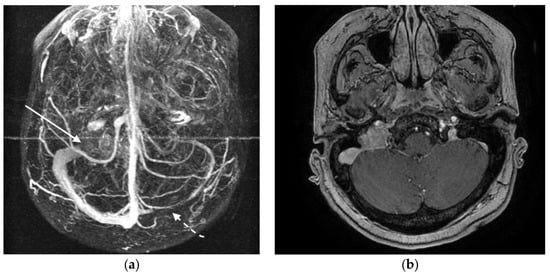

3.3.2. Case 2

4.4. Cerebral Sinus Affection